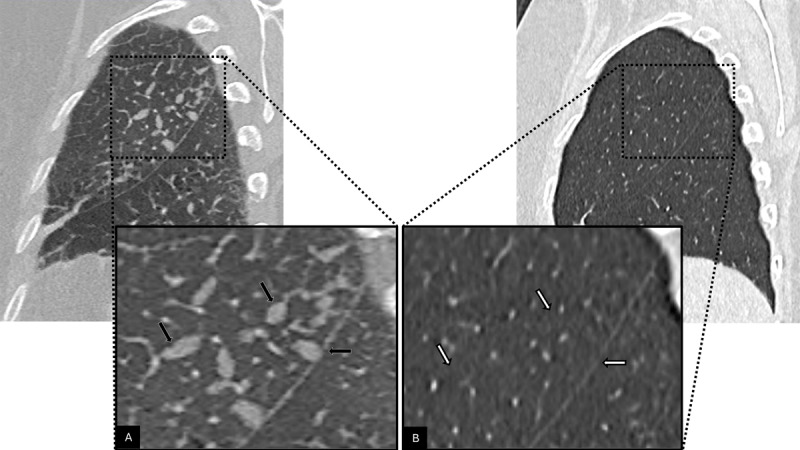

Teaching point: Transient interlobular septal nodules displaying a characteristic branched 'pearl-like' pattern may reflect acute pulmonary lymphatic overload and should not be mistaken for other common pathological processes.

教学要点:短暂性小叶间隔结节表现为特征性的“珍珠样”分支,可能反映急性肺淋巴负荷过重,不应与其他常见病理过程相混淆。